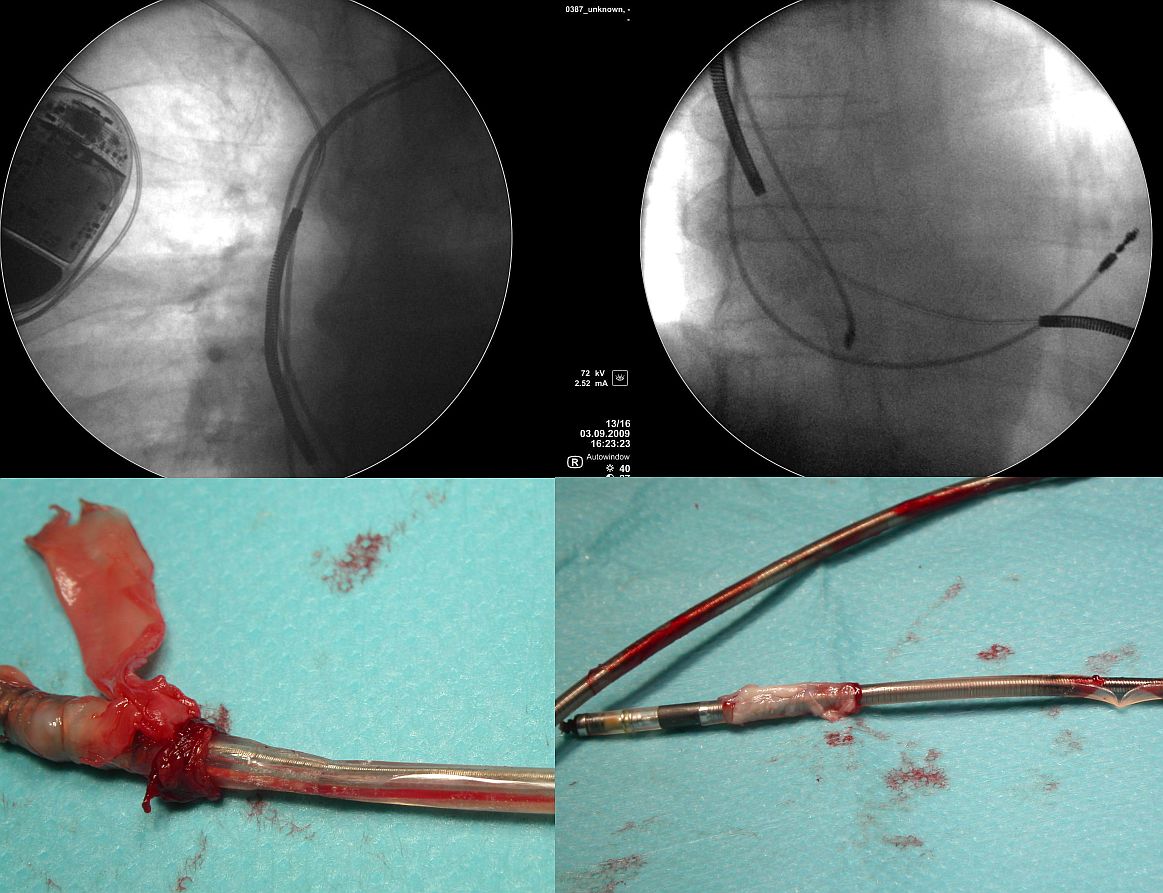

- Realia kliniczne. W mojej osobistej ocenie,

niepodważalne fakty przedstawione przez firmę St Jude

Medical dotyczące objawów i diagnostyki przetarć osłonek

zewnętrznych nie oddają całej, bardziej złożonej

problematyki. Badania przeprowadzone przez firmę dotyczyły

elektrod defibrylujących, w których stwierdzono

nieprawidłowości działania elektrody. Nie są to

badania elektrod różnych typów elektrod (w tym

stymulatorowych), usuniętych z innych przyczyn niż

dysfunkcje elektrod. Pamiętajmy, że większość przetarć

elektrod innych niż defibrylatorowe pozostaje niemymi

"elektrycznie"; jednak ich następstwa bywają

znacznie poważniejsze. Elektrody stymulatorowe, w większości

konstrukcji koaksjalnej, mają dużo wolnych przestrzeni

wewnętrznych. Najważniejsza z nich to przestrzeń wokół

spirali zewnętrznej, pod zewnętrzną osłonką

elektrody. Przetarcie osłonki z osłonięciem spirali

powoduje, że do tej przestrzeni wnika krew. Przestrzeń

ta często miewa połączenie z lożą stymulatora, gdzie

dochodzi również do często niewidocznych gołym okiem

mikrouszkodzeń osłonki. W przypadku miejscowej infekcji

loży, przetarta elektroda stanowi idealną autostradę

prowadzącą z loży do wnętrza serca, na której

drobnoustroje chronione są przed mechanizmami obronnymi

organizmu i antybiotykami na całej jej długości. Z

kolei w przypadku przejściowej / przemijającej

bakteriemii - drobnoustroje mogą wniknąć do tej

przestrzeni też mając idealne warunki do rozwoju. Do

postawienia tej hipotezy upoważniło nas zaobserwowanie

dwóch zjawisk: częstej obecności wegetacji w miejscu

przetarcia elektrod oraz wybitnie częstego współistnienia

zapalenia wsierdzia z przetarciem elektrod. O ile w całości

naszego materiału IZW stanowiło wskazanie do usunięcia

elektrod u 17% pacjentów, to wśród pacjentów z IZW

przetarcie osłonki elektrody z perforacją stwierdzono w

46 %, u pacjentów z infekcją miejscową - jedynie w 15%

i u pacjentów u których elektrody usuwano ze wskazań

nieinfekcyjnych (głównie nadmiar zbędnych elektrod) - w

23%. Oczywiście że jakkolwiek nie należy traktować

przetarcia elektrody jako jedynej przyczyny tzw.

odelektrodowego zapalenia wsierdzia, to jednak zjawisko to

wydaje się mieć istotne znaczenie patogenetyczne.